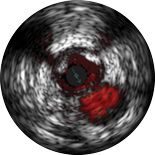

ChromaFlo обеспечивает простую оценку аппозиции стента, размера просвета сосуда и других параметров за счет выделения кровотока красным цветом на изображении в одно нажатие кнопки. Функция ChromaFlo доступна на системах для интервенционных вмешательств Philips.

Эта функция создана для быстрой оценки размера просвета сосуда и аппозиции стента; она облегчает определение ветвей сосудов, диссекций и тромбов, а также упрощает оценку распределения бляшек в области бифуркаций. Функция ChromaFlo выделяет кровоток красным цветом, что помогает:

Во время визуализации не требуется выполнять промывание или какие-либо специальные процедуры. Просто активируйте функцию ChromaFlo одним нажатием кнопки.

Функция ChromaFlo совместима с цифровыми катетерами для ВСУЗИ Philips Eagle Eye Platinum.